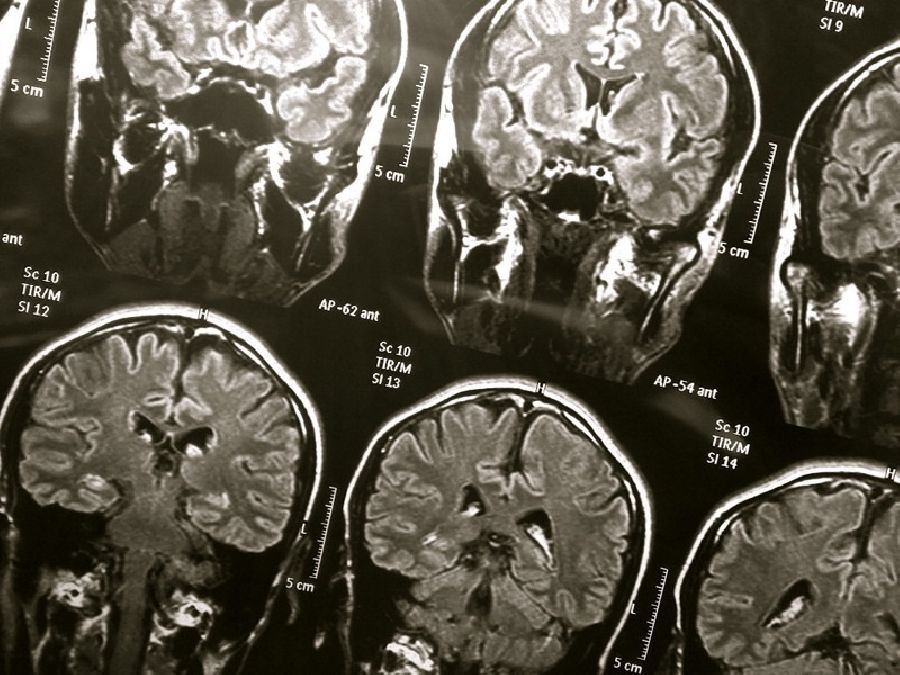

Encuentran una vía para abordar el deterioro de la barrera hematoencefálica en el Alzheimer

Tras desarrollar un modelo de laboratorio de la barrera hematoencefálica humana (BHH), los neurocientíficos del Instituto Picower para el Aprendizaje y la Memoria del Instituto Tecnológico de Massachusetts (MIT) han descubierto cómo el gen de riesgo de enfermedad de Alzheimer más común provoca que las placas de proteína amiloide rompan la vasculatura del cerebro y han demostrado que pueden prevenir el daño con medicamentos ya aprobados para uso humano.

En el nuevo estudio, publicado en la revista \'Nature Medicine\', los investigadores identificaron el tipo específico de células vasculares (pericitos) y la vía molecular (calcineurina / NFAT) a través de la cual la variante APOE4 promueve la patología CAA.

Para validar aún más la relevancia clínica de estos hallazgos, el equipo también analizó la expresión de APOE en muestras de vasculatura cerebral humana en la corteza prefrontal y el hipocampo, dos regiones afectadas de manera crucial en la enfermedad de Alzheimer. De acuerdo con el modelo BBB del laboratorio del equipo, las personas con APOE4 mostraron una mayor expresión del gen en la vasculatura, y específicamente en los pericitos, que las personas con APOE3.